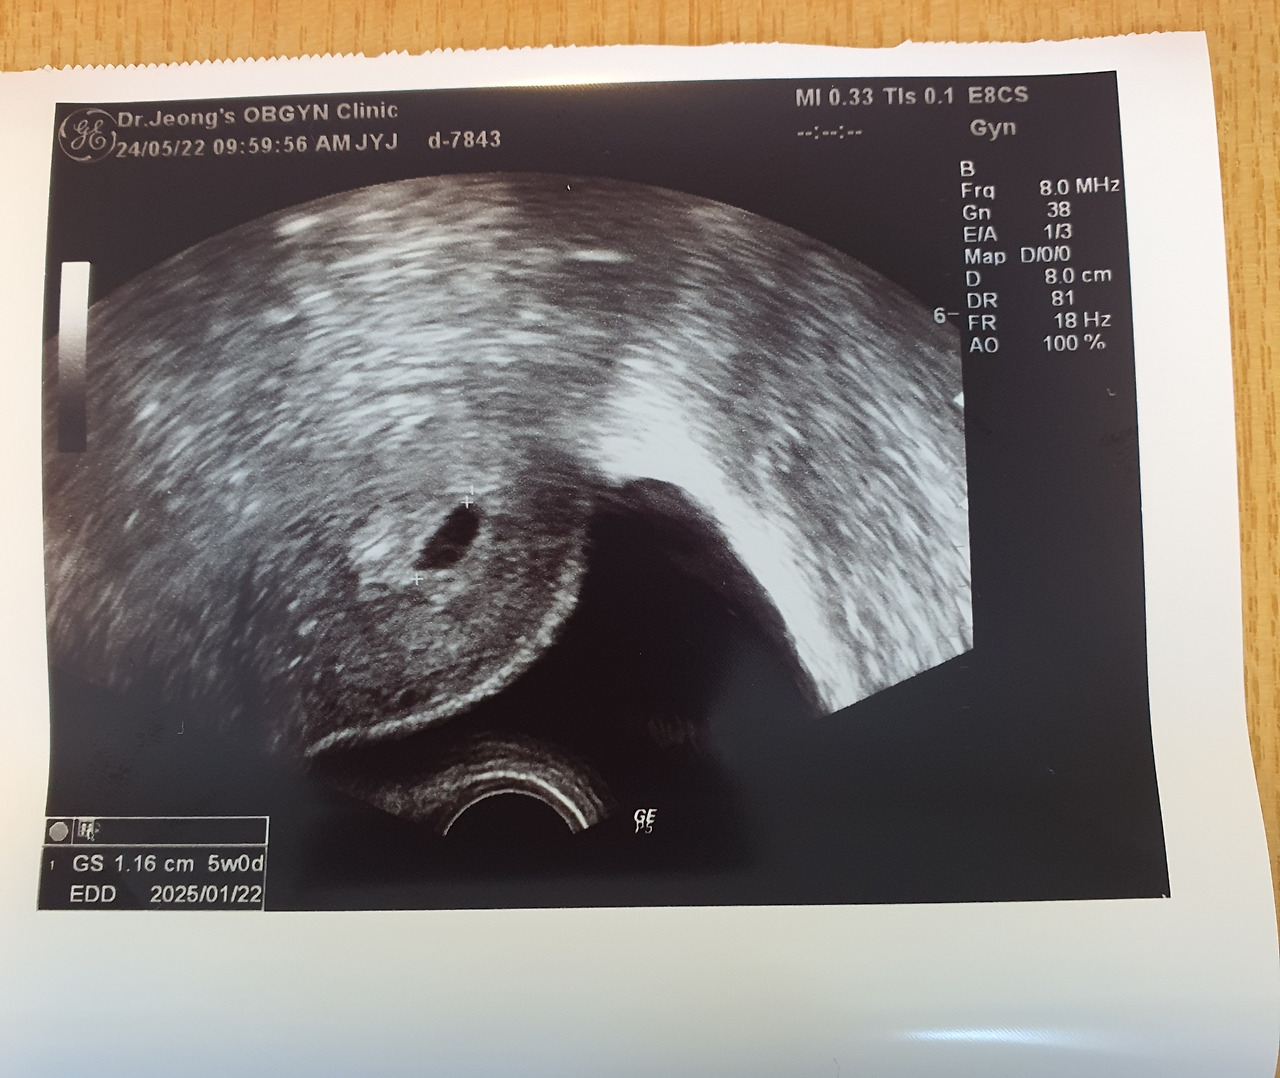

임신 4~5주

산부인과를 방문해 착상을 확인한 다음, 아기집은 아직 없다는 말을 듣고 임신확인서를 못 받은 날.

그리고 그 후 일주일, 산부인과에서 심장소리를 들었다.

산부인과에서 임신확인서과 산모수첩을 받은 날. 기분이 얼떨떨했다.

의사 선생님이 뱃 속 아이의 심장소리를 들어보자며, 심장소리를 들려주셨다.